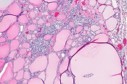

Figure 1, Figure 2, Figure 3, Figure 4, Figure 5, Figure 6, Figure 7, Figure 8

Figure 5.MEN1 syndrome demonstrating goitrous enlargement of thyroid gland with colloid impaction13.